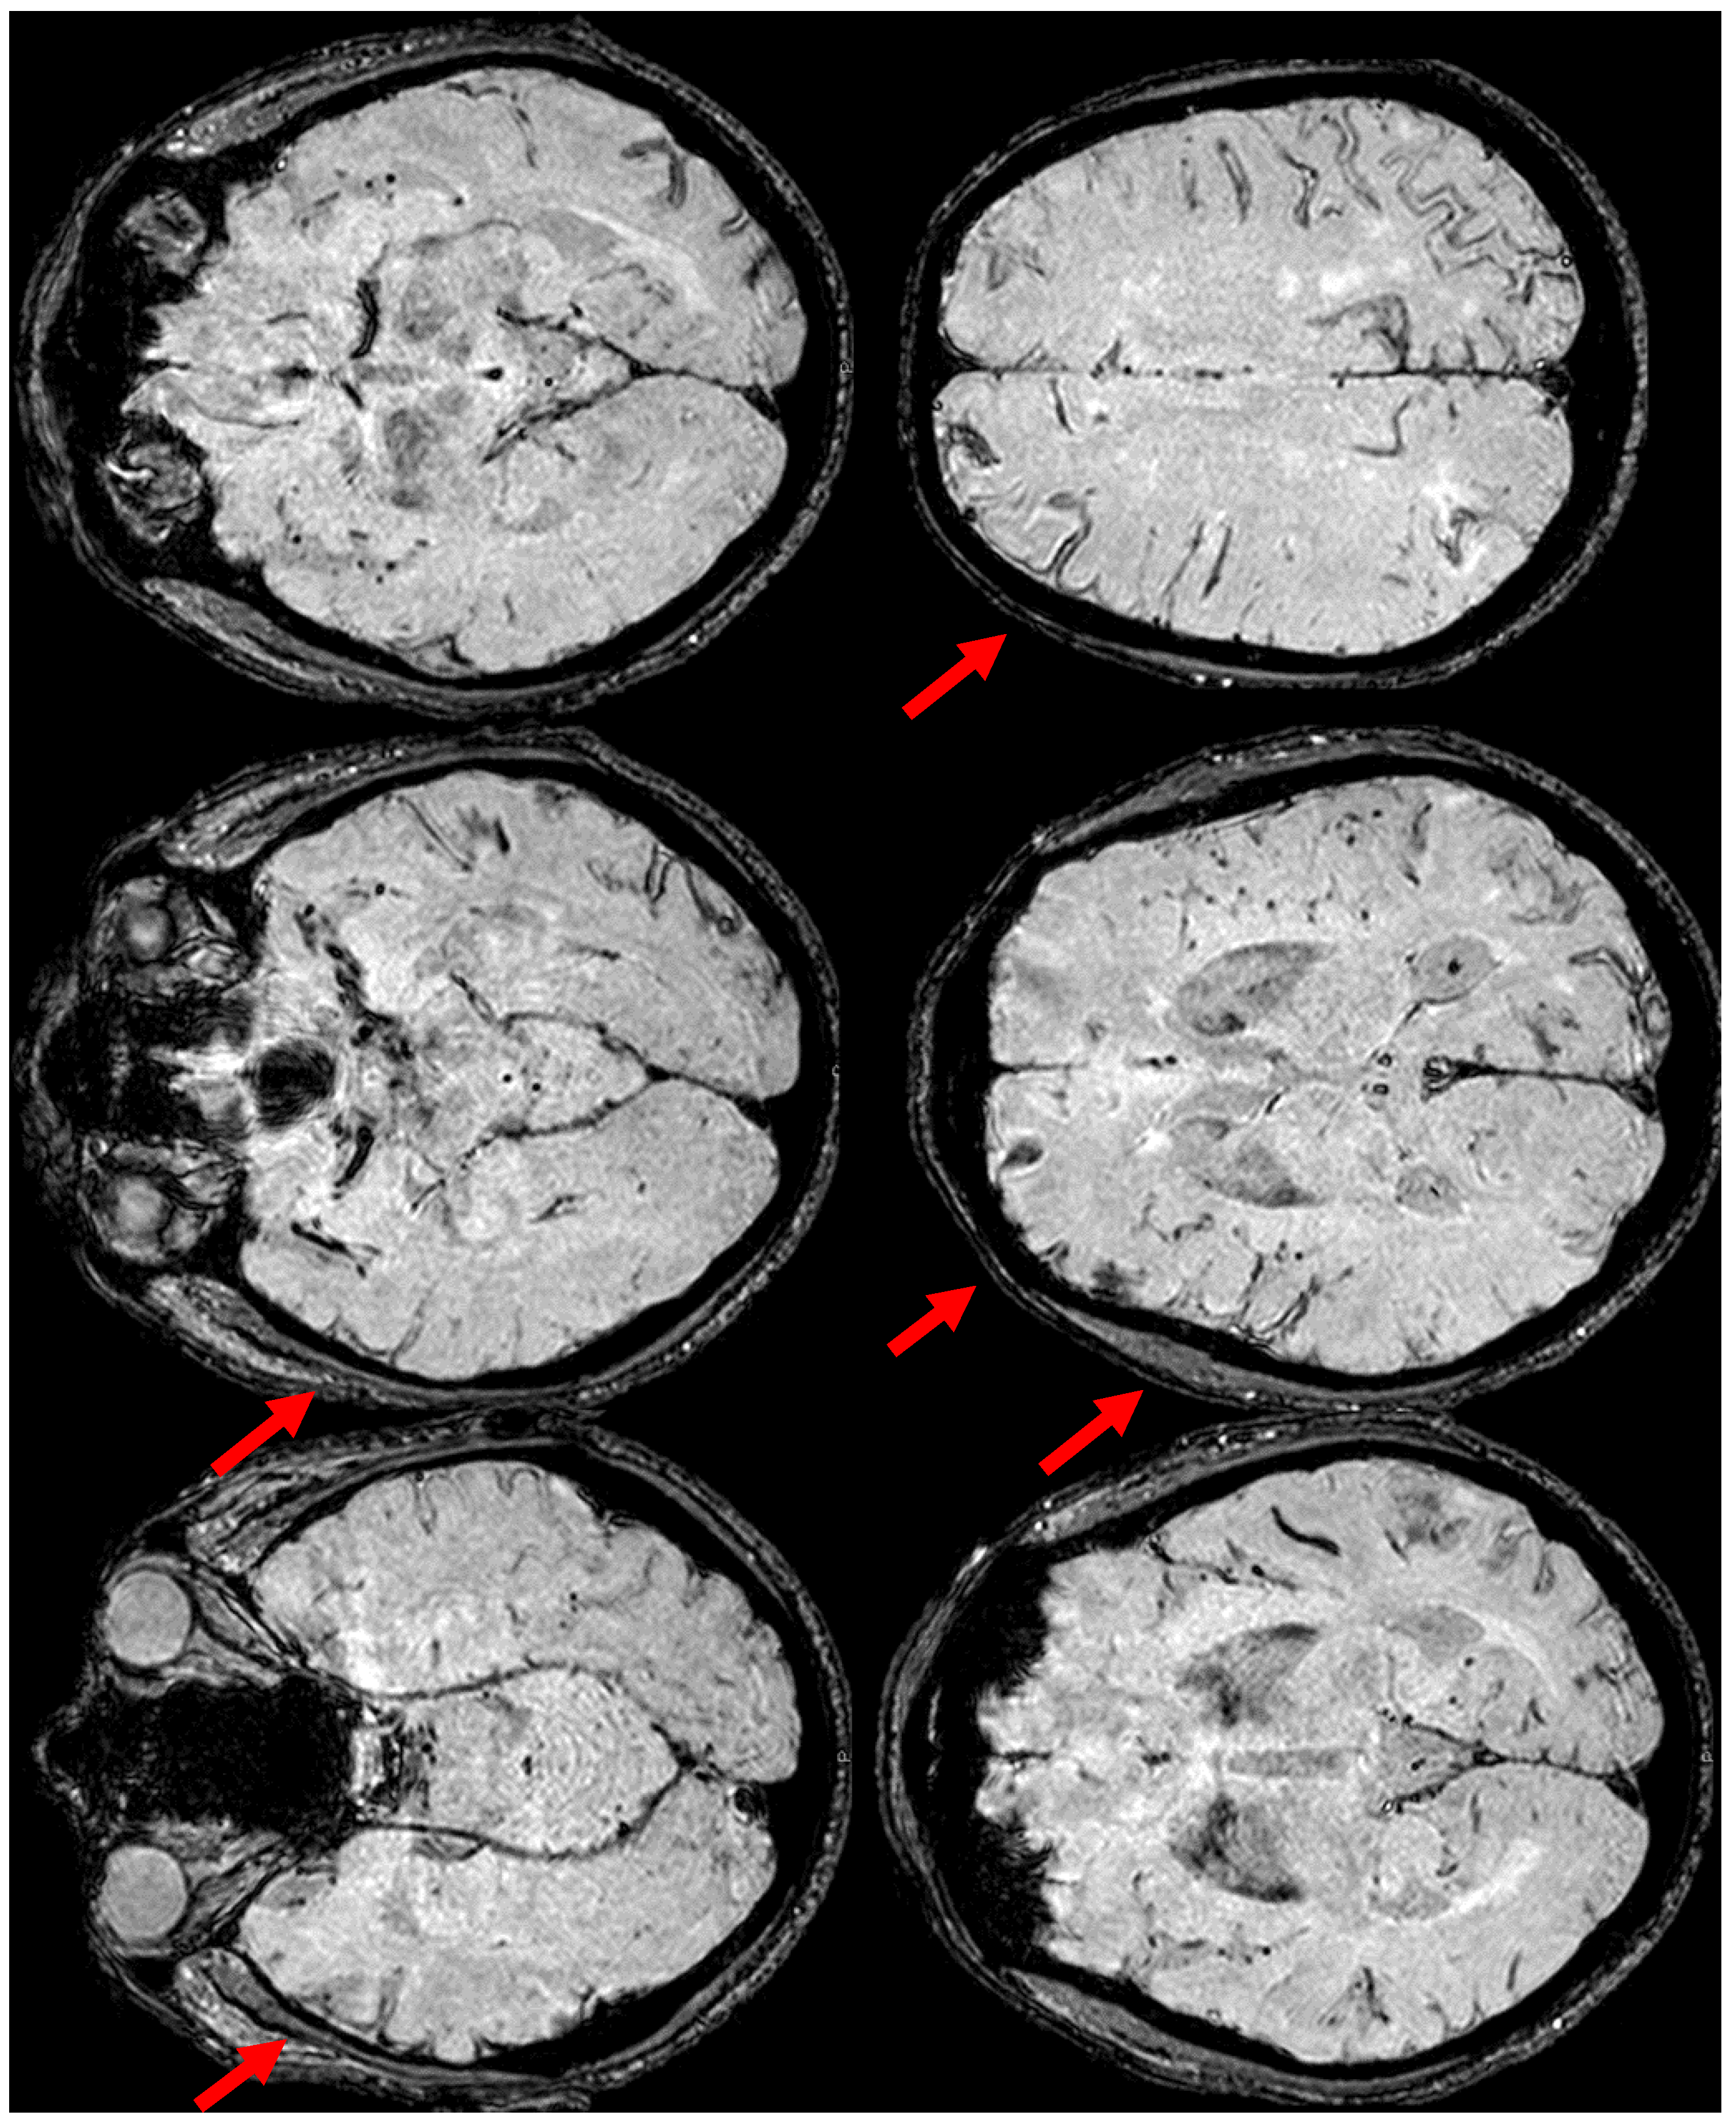

2. December 2013: Sulcal SAH and TFNEs

6. December 2017: Recurrent SAH